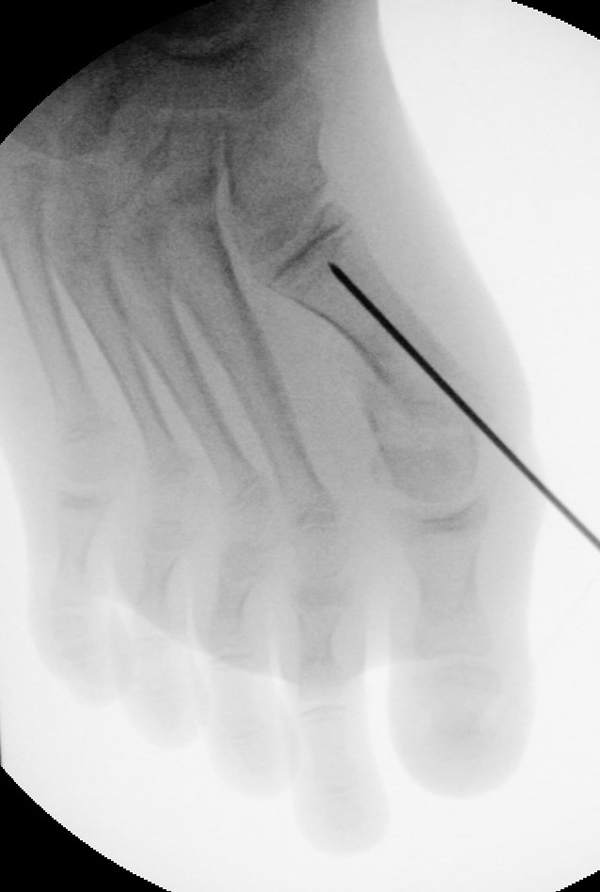

=> Risikoabwägung der radiologisch leicht erhöhten Strahlenbelastung intraoperativ

In der minimalinvasiven Fußchirurgie ist es unabdingbar, die Fräse in ihrer Position zum Knochen radiologisch zu kontrollieren, damit vulnerable Wachstumsfugen oder angrenzende Gelenke nicht verletzt werden. Zu diesem Zweck werden mit einem Bildwandler während der Operation die genaue Position der Fräse und der Osteotomieverlauf überprüft, was die Strahlenbelastung im Vergleich zu offenen Verfahren erhöht. Diese Strahlenbelastung hat potenziell einen schädigenden Einfluss auf den noch blutbildenden Knochen von Heranwachsenden. Gesicherte Landmarken am Fuß können die notwendige Zahl der Röntgenbilder und damit die Strahlung minimieren. Ist es erforderlich, mehrere Knochen zu osteotomieren, wie zum Beispiel im Bereich der Kleinzehen, werden anhand der Landmarken kleine Injektionsnadeln auf Höhe der geplanten Osteotomien vorgelegt und radiologisch im Bildwandler (BV) dokumentiert (Abb. 11). Ein solches Bild schafft eine gute Orientierung, sodass auf radiologische Kontrollen intraoperativ weitestgehend verzichtet werden kann.

Abb. 11: Lokalisation mehrerer Stichinzisionen mit einem Röntgenbild.